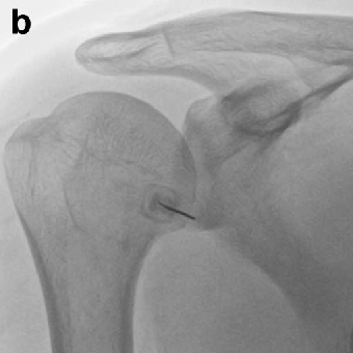

어깨 관절낭 수압 팽창술

염증에 의한 관절낭과 회전근개의 유착을 제거하기 위해 유착을 녹이는 효소제를 주사 할 수 있으며 염증과 부종을 줄여주기 위해 항염증제를 같이 주입합니다. 어깨 관절낭에 최대한 많은 주사액을 주입함으로써 물리적, 화학적으로 유착을 박리하고 조직의 염증과 부종을 줄여줍니다.